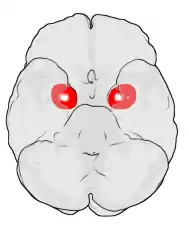

Además, resultados recientes sugieren que las diferencias sexuales en la amígdala podrían correlacionarse con diferencias hemisféricas de la amígdala. Cahill y otros[6] sugieren una teoría «derecha-varón, izquierda-mujer» de la actividad de la amígdala. Así, las conexiones con la amígdala derecha facilitan un mejor seguimiento o vigilancia de estímulos externos, y las conexiones con la amígdala izquierda facilitan un mejor seguimiento o vigilancia de estímulos internos.